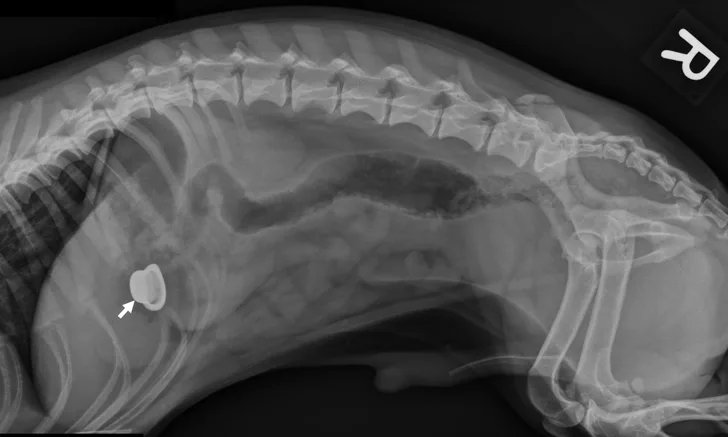

Bobs for dogs x ray top, A Visual Guide to GI Obstruction on Radiographs top

A Visual Guide to GI Obstruction on Radiographs

A Visual Guide to GI Obstruction on Radiographs

Thought you would find the radiographs of my pet rat Bob s badly sprained back right leg interesting. r Radiology top, Thought you would find the radiographs of my pet rat Bob s badly sprained back right leg interesting. r Radiology top, Newfoundland Dog Health Center top, X ray of dog lateral view with Gastric dilatation volvulus GDV or stomach twists Double bubble pattern indicates stomach torsion has occurred Veterinary medicine and Veterinary anatomy Concept. Stock... top, A Visual Guide to GI Obstruction on Radiographs top, Newfoundland Dog Health Center top, How Nestle s leg almost got amputated Dr Phil Zeltzman s Blog top, Radiography of the Small Animal Skull Temporomandibular Joints Tympanic Bullae Today s Veterinary Practice top, Loving Paws Pet Clinic Low stress veterinarian in Savoy IL X rays top, A Visual Guide to GI Obstruction on Radiographs top, Small Animal Elbow and Antebrachium Radiography Today s Veterinary Practice top, Understanding X rays can save dollars and lives WCVM Today Western College of Veterinary Medicine University of Saskatchewan top, A Visual Guide to GI Obstruction on Radiographs top, Radiography of the Small Animal Skull Temporomandibular Joints Tympanic Bullae Today s Veterinary Practice top, You removed how much of Mimi s jaw Dr Phil Zeltzman s Blog top, Dog X rays Variety of Radiographs Taken on Dogs top, Dog X rays Variety of Radiographs Taken on Dogs top, X ray Dog Anterior Image Photo Free Trial Bigstock top, X Ray Normal Forelimb Dog Stock Photo 689852953 Shutterstock top, DOG BOWEL OBSTRUCTION X RAY Stock Photo Image of skeleton pain 30050362 top, xray of dogs chest showing heart disease Stock Photo Alamy top, Bobby Bob Bob Tamara Kenneally Photography top, BOBs Kennels top, Radiographs for Dogs Bioscint top, Dog X rays Variety of Radiographs Taken on Dogs top, Pets will eat the strangest things top, Dog X rays Variety of Radiographs Taken on Dogs top, Lateral X ray Radiograph Left Forelimb Puppy Stock Illustration 1344763586 Shutterstock top, Top 5 Tips on Radiographic Diagnosis of Obstructive Foreign Bodies top, Dog X rays Variety of Radiographs Taken on Dogs top, Right Lateral Chest X ray Radiograph Dog Stock Illustration 1337012921 Shutterstock top, Dog X rays Variety of Radiographs Taken on Dogs top, Abdominal X Rays Made Easy top, Old Chapel Veterinary Clinic Canine elbow dysplasia ED is a disease of the elbows of dogs caused by growth disturbances in the elbow joint. Elbow dysplasia is most often seen in top, Hi Ferg swallowed a piece of flat rubber ball about 1 x2.5 a week ago. She has been asymptomatic. Xrays were taken and radiologist. PetCoach top.

Thought you would find the radiographs of my pet rat Bob s badly sprained back right leg interesting. r Radiology top, Thought you would find the radiographs of my pet rat Bob s badly sprained back right leg interesting. r Radiology top, Newfoundland Dog Health Center top, X ray of dog lateral view with Gastric dilatation volvulus GDV or stomach twists Double bubble pattern indicates stomach torsion has occurred Veterinary medicine and Veterinary anatomy Concept. Stock... top, A Visual Guide to GI Obstruction on Radiographs top, Newfoundland Dog Health Center top, How Nestle s leg almost got amputated Dr Phil Zeltzman s Blog top, Radiography of the Small Animal Skull Temporomandibular Joints Tympanic Bullae Today s Veterinary Practice top, Loving Paws Pet Clinic Low stress veterinarian in Savoy IL X rays top, A Visual Guide to GI Obstruction on Radiographs top, Small Animal Elbow and Antebrachium Radiography Today s Veterinary Practice top, Understanding X rays can save dollars and lives WCVM Today Western College of Veterinary Medicine University of Saskatchewan top, A Visual Guide to GI Obstruction on Radiographs top, Radiography of the Small Animal Skull Temporomandibular Joints Tympanic Bullae Today s Veterinary Practice top, You removed how much of Mimi s jaw Dr Phil Zeltzman s Blog top, Dog X rays Variety of Radiographs Taken on Dogs top, Dog X rays Variety of Radiographs Taken on Dogs top, X ray Dog Anterior Image Photo Free Trial Bigstock top, X Ray Normal Forelimb Dog Stock Photo 689852953 Shutterstock top, DOG BOWEL OBSTRUCTION X RAY Stock Photo Image of skeleton pain 30050362 top, xray of dogs chest showing heart disease Stock Photo Alamy top, Bobby Bob Bob Tamara Kenneally Photography top, BOBs Kennels top, Radiographs for Dogs Bioscint top, Dog X rays Variety of Radiographs Taken on Dogs top, Pets will eat the strangest things top, Dog X rays Variety of Radiographs Taken on Dogs top, Lateral X ray Radiograph Left Forelimb Puppy Stock Illustration 1344763586 Shutterstock top, Top 5 Tips on Radiographic Diagnosis of Obstructive Foreign Bodies top, Dog X rays Variety of Radiographs Taken on Dogs top, Right Lateral Chest X ray Radiograph Dog Stock Illustration 1337012921 Shutterstock top, Dog X rays Variety of Radiographs Taken on Dogs top, Abdominal X Rays Made Easy top, Old Chapel Veterinary Clinic Canine elbow dysplasia ED is a disease of the elbows of dogs caused by growth disturbances in the elbow joint. Elbow dysplasia is most often seen in top, Hi Ferg swallowed a piece of flat rubber ball about 1 x2.5 a week ago. She has been asymptomatic. Xrays were taken and radiologist. PetCoach top.